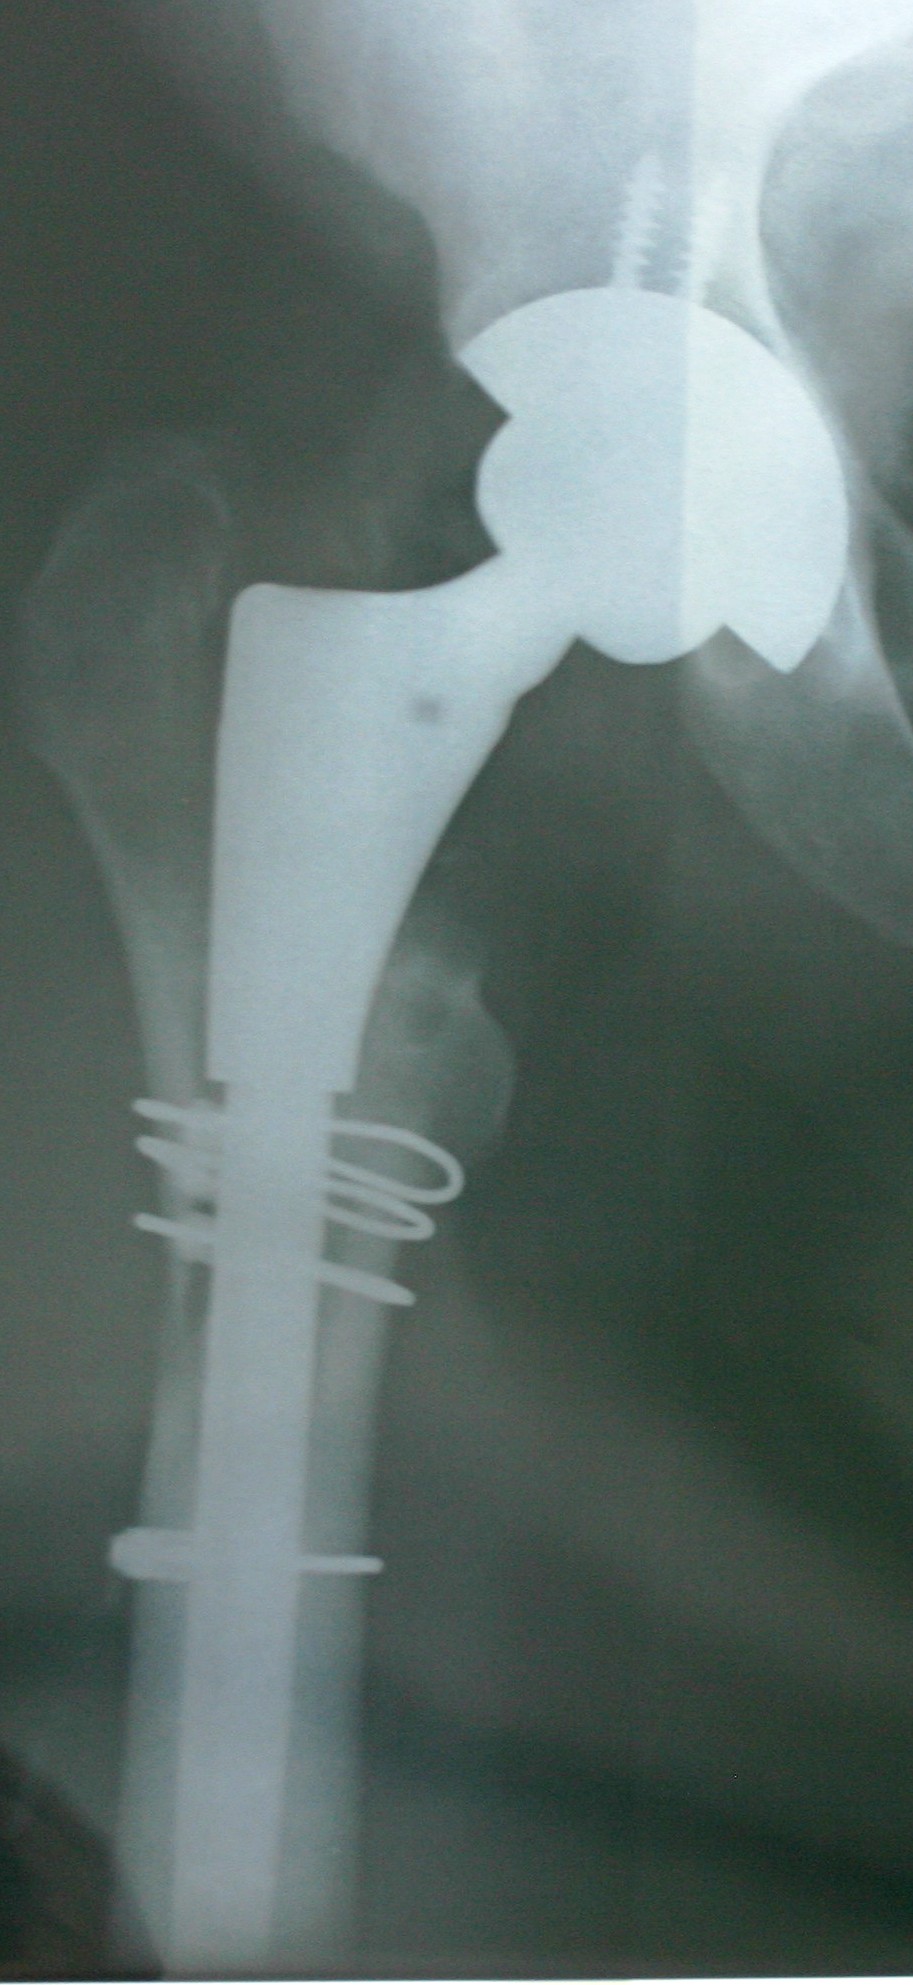

And here is the X-Ray of the hardware underneath!